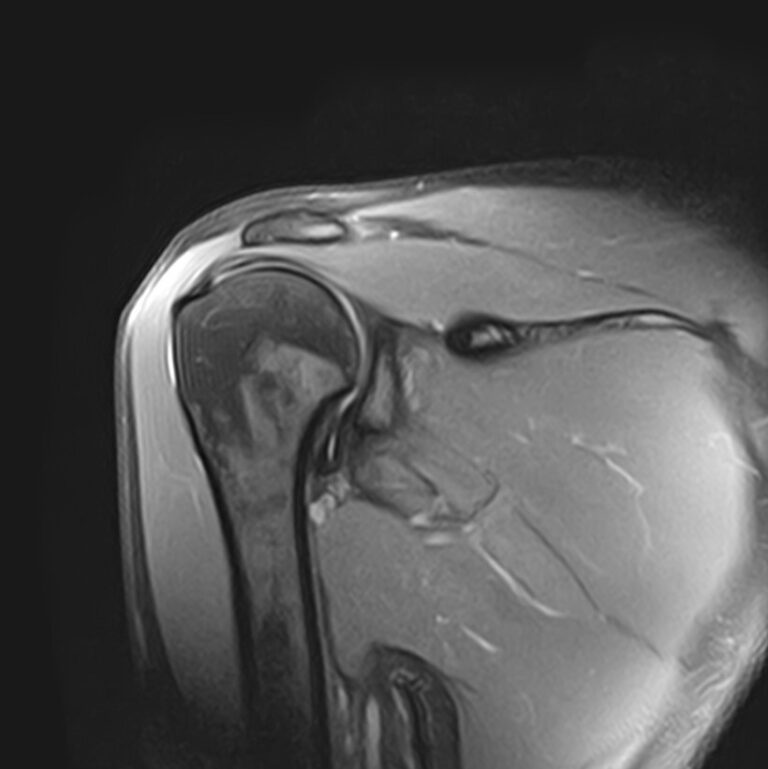

Плечевой сустав является наиболее подвижным сочленением, которое образовано лопаткой и головкой плечевой кости. У сустава нет мощных связок, он укрепляется мышцами плечевого пояса, окружающими его по типу корсета. Суставную капсулу образуют короткие связки, расположенные вокруг сустава. Благодаря такому строению сустав отличается высокой подвижностью, но при этом склонностью к вывихам. Полость сустава заполнена синовиальной жидкостью, питающей хрящи и служащей смазкой для них.

Метод МРТ позволяет оценить состояние всех анатомических областей плечевого сустава,  включая костную структуру, суставную капсулу, полость сустава с выстилающей его синовиальной оболочкой, связки, сухожилия, мышцы и окружающие мягкие ткани.